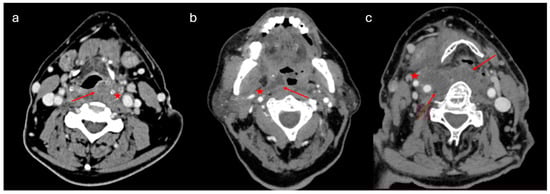

PMA diagnosis was the second most common diagnosis, following peritonsillar abscesses, involving 106 adults (female/male ratio: 21/85, mean age: 51 ± 14.1 years). (Table 1). Associated comorbidities included hypertension (n = 22), dyslipidemia (n = 20), heart disease (n = 8), thyroid disease (n = 8), diabetes mellitus (n = 7), asthma (n = 5), anemia (n = 3), renal insufficiency (n = 1), and rheumatoid arthritis (n = 1). Eight patients had a history of tonsillectomy. CT scans with contrast were conducted to confirm the diagnosis (Figure 3).

Although clinical findings are of the greatest importance in the suspicion of a PMA, a CT scan with contrast is the “gold standard” to set the diagnosis [7] (Figure 3 and Figure 5). Abscess protrusion into the pharyngeal lumen may give the false impression of a parapharyngeal abscess; however, the PMS is located in the lateral pharyngeal wall, between the pharyngeal mucosa and the pharyngeal constrictors, extending under the hyoid bone and passing medially to it. On the contrary, other spaces extend laterally to the hyoid bone (e.g., carotid space), whereas, for others (e.g., parapharyngeal space), it represents their lower border. Ultrasonography cannot identify the PMS adequately, while MRI may also be of use in selected cases [7]. The high diagnostic accuracy of MRI can be utilized in order to specify the anatomic relation of the abscess with the pharyngeal constrictors, differentiating between PMAs and deeper-extending abscesses [11]. However, the practical need for imaging and the cost-effectiveness can be controversial, as a significant number of cases can resolve rapidly. Nevertheless, unless strongly contraindicated, imaging is highly recommended, so that deeper counterpart involvement may be excluded, especially in cases with severe symptoms and clinical findings.

Figure 3. CT scan with contrast of pharyngeal mucosal space abscesses (PMAs). (a) Right-side PMA protruding into the pharyngeal lumen, located towards the lateral pharyngeal wall, just under the pharyngeal mucosa and medial to the pharyngeal constrictors, away from the ipsilateral carotid artery and the internal jugular vein. (b) Right-side PMA protruding into the pharyngeal lumen and passing medially to the hyoid bone, away from the ipsilateral carotid artery and the internal jugular vein.